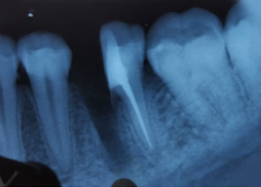

Pre-OP IOPAR